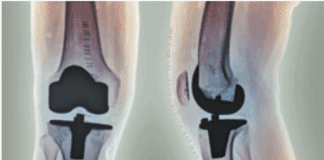

Preparing for Joint Replacement